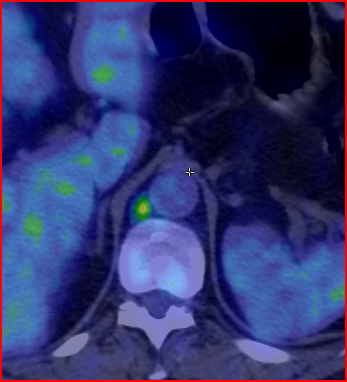

5. Multiplex bone metastases. Bone scintigraphy, anterior (a) and posterior (b) whole body scans. SPECT-CT sagittal plane, fusion image (c) and CT image (d). Obvious bone structural changes cannot be identified on the CT scan yet.

The examination is appropriate for staging a malignant process and following-up bone metastases. It is clinically most suitable for lesions that frequently present bone metastasis, primarily in case of prostate-, breast-, lung cancer and neuroblastoma. It is, however only indicated in cases where the soft tissue involvement of the tumor is big enough to suggest a higher incidence of bone metastasis; before radical surgeries and for the selection of patients who would benefit form a palliative radionuclide therapy. Otherwise, scintigraphy is advisable in case of any primary tumor, if the suspicion for metastasis is raised, e.g.: bone pain, pathologic radiological or lab results (elevated serum ALP and tumor marker levels). Bone metastases in most cases are located in bones that contain red bone marrow (skull, vertebrae, ribs, sternum, pelvic bones and the proximal bone segments of the limb) and usually show a multiplex appearance. Activity increase can be seen typically, metastases that cause activity decrease are rare; they could occur in cases of thyroid gland tumor, renal carcinoma, lymphoma and multiple myeloma. Solitary lesions or a few lesions only, due to the aspecific nature of the examination, cause a differential diagnostic problem in many cases, for example vertebral degenerative processes can mimic metastatic activity. Equivocal lesions usually require further, targeted radiological investigations. A negative X-ray examination does not rule out the possibility of a metastatic lesion, since the isotope scan is more sensitive. Therefore, it is possible that it could already be detecting an existing metastasis, while X-ray is still insensitive and unable to show the lesion. (Figure 5.)

SPECT examination of the spine can help in the precise lesion localization within a single vertebra. It is especially useful, since the different pathologic bone processes occur in different predilection sites of the vertebral bone. Bone metastases are commonly located in the dorsal aspect of the vertebral body. Degenerative processes involve mostly the vertebral edge as in the case of spondylophytes in spondylosis. Finally, spondolyathrosis is usually located at the intervertebral facet joints.